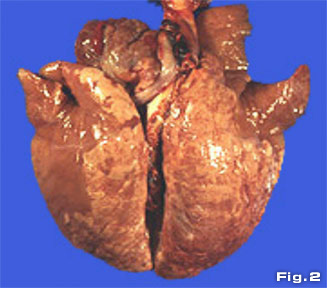

El período de incubación de la NEP, así

como el período activo de enfermedad (aquel en el que

se manifiestan síntomas y signos clínicos) probablemente

dependan de la exposición de los animales susceptibles

y de la virulencia de la cepa comprometida. Estos cerdos desarrollan

lesiones pulmonares evidentes a partir de los 7 a los 10 días

después de la infección (Fig.

2).